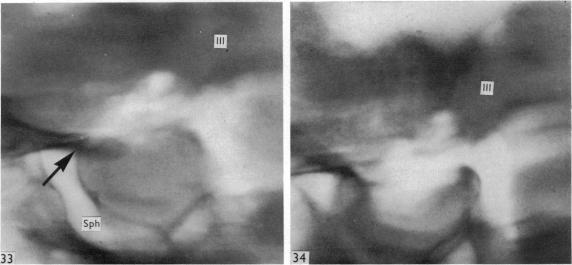

Surgical aspects of the anatomy of the sphenoidal sinuses and the sella turcica.

J Anat. 1977 Dec;124(Pt 3):541-53.